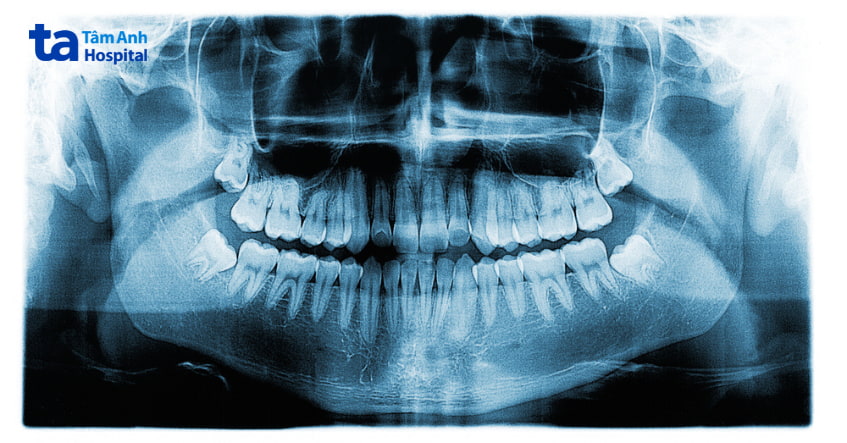

Điều người bệnh cần làm khi xuất hiện các triệu chứng này là hãy nhanh chóng đến bệnh viện để được bác sĩ chuyên khoa Răng Hàm Mặt tư vấn và hướng dẫn điều trị kịp thời. Thông qua các triệu chứng nêu trên, bác sĩ sẽ thăm khám tổng quát, chụp phim X – quang để kiểm tra hướng và góc mọc của răng khôn để đưa ra chẩn đoán chính xác nhất.